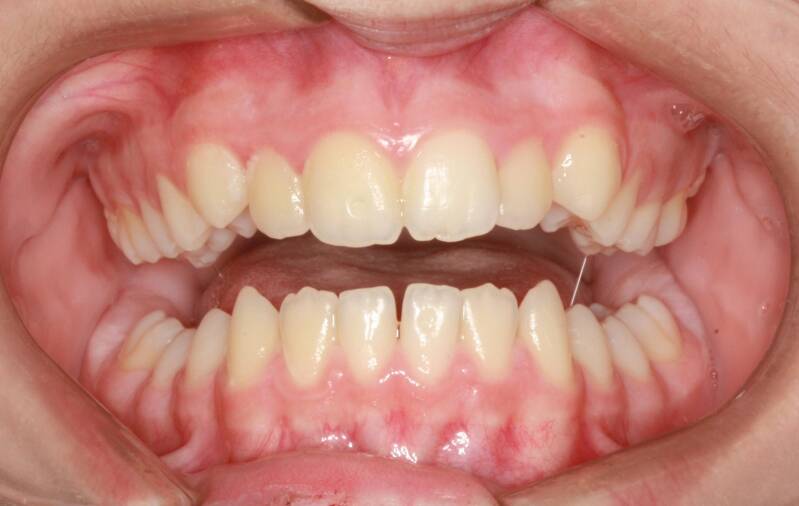

FOTO INIZIALI PRE TRATTAMENTO ORTODONTICO

Questo mese vi presentiamo G.G. f. di15aa. Ha una seconda classe suddivisione destra molare e canina. richiesta Allineamento.